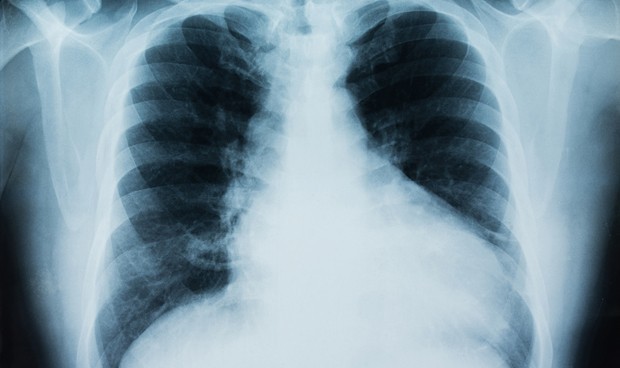

Inesperada respuesta inmune del Covid-19 en los pulmones

El SARS-CoV-2 activa en las células pulmonares una respuesta inmune “inesperada”, en palabras de los autores de un estudio publicado en Science Immunology, que los lleva a pensar que esté relacionada con la afectación a dicho órgano y la gravedad de la enfermedad.

Se trata del sistema inmune del complemento, un conjunto de proteínas que se derivan del hígado y que normalmente colaboran con los anticuerpos para luchar contra patógenos presentes en el torrente sanguíneo.

Sin embargo, “se halló inesperadamente que el sistema del complemento era una de las rutas intracelulares más altamente inducidas por la infección de SARS-CoV-2 en las células pulmonares epiteliales”, explica el equipo liderado por Bingyu Yan, del Departamento de Bioquímica de la Universidad de Purdue, en Estados Unidos.

La infección en estas células generó la activación de la molécula C3a, que forma parte del sistema del complemento y que se relacionó con una respuesta inflamatoria de las células pulmonares.